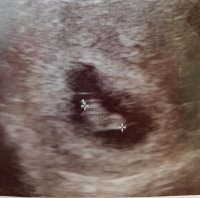

Fikk se et hjerte som banket. Det er jo ikke så mye å se så tidlig, og for tidlig til å sette termin sa legenVar på UL idag, min beregning var 7+4, noe som så ut til å stemme. Tok utvendig UL, jeg trodde de bare brukte innvendig frem til ca 12 uker. Fikk med et bildeFikk se et hjerte som banket. Det er jo ikke så mye å se så tidlig, og for tidlig til å sette termin sa legen